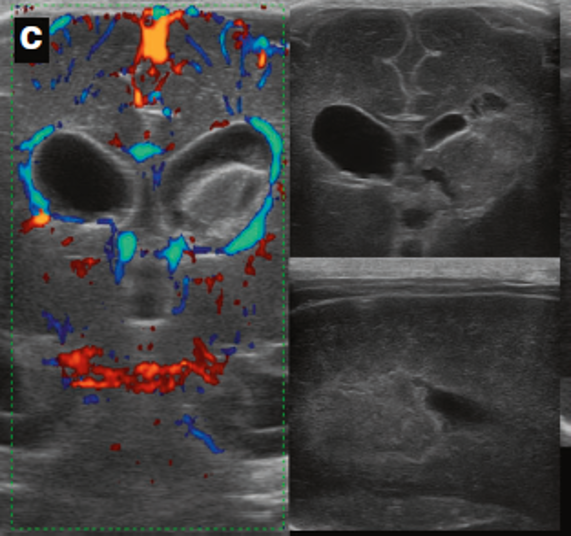

Neonatology PVHI Doppler Example Image